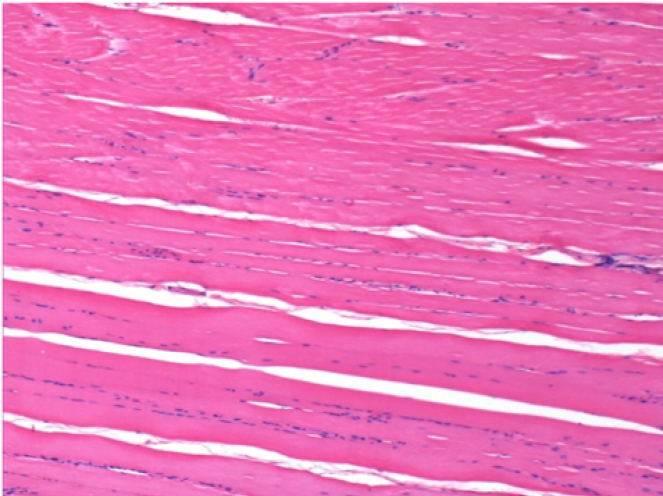

3 months (D90)after Endopeel Injection 0.1ml in the right pretibial muscle.